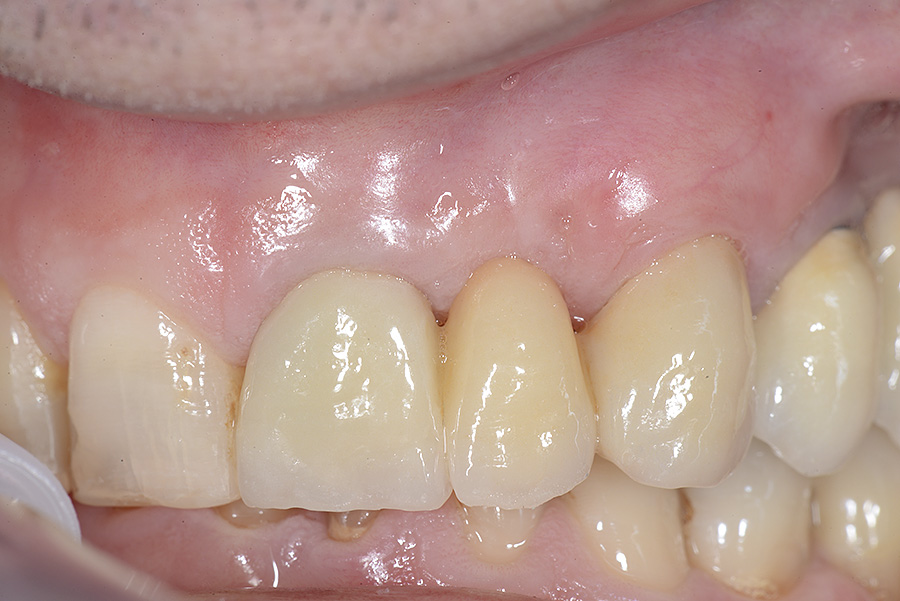

PREMESSA: in seguito all’estrazione dell’incisivo laterale superiore di destra, resasi necessaria per cause batteriche, si decide di affrontare il caso con il posizionamento di un impianto in sostituzione dell’elemento mancante dopo guarigione del sito infetto. Con tecniche rigenerative sia dei tessuti ossei mancanti a causa dell’infezione pregressa, sia dei tessuti gengivali che appaiono inizialmente troppo spostati in alto, si ripristina una corretta morfologia delle parabole (contorni) gengivali e delle papille interdentali (triangoli di gengiva tra due denti vicini).

Vengono utilizzati 2 tipi di provvisori: il primo, cementato ai denti vicini, viene utilizzato dal momento dell’estrazione del dente fino ad impianto osteointegrato (circa 6 mesi); il secondo, avvitato direttamente all’impianto, ha una funzione di prova estetica ma soprattutto di guida per la maturazione dei tessuti gengivali peri-implantari portandoli verso la maturazione completa prima di posizionare la corona finale in disilicato di litio.